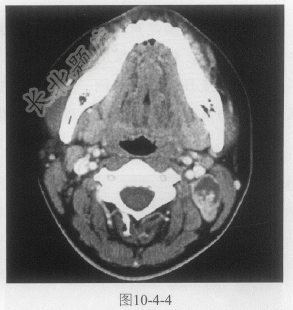

- 单项选择题患者女性,21岁,发现左颈肿物1个月,如图10-4-4,以下诊断最可能的是:

A、左侧颈部淋巴管瘤

B、左侧颈部淋巴结转移

C、左侧颈部鳃裂囊肿

D、左侧颈部淋巴结结核

E、左侧颈部神经鞘瘤